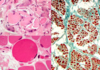

All three of these images are related to the same disease: what is that disease?

Dermatomyositis

Perifascicular atrophy with small muscle cells at teh edges of the fasicle with immune inflammatory accumulations

Key: small vessel damage is very important in this disease and can see that in the bottom picture

What is this?

Inclusion body myositis

- Most common inflammatory myopathy in persons 65+

- Rimmed vacuoles with basophilic granules at the periphery

- Vacuolated fibers stain with congo red

- Inflammatory infiltrate similar to polymyositis but also share some features of neurodegenerative origin

Additional image with examples attached to also show variability of inflammation